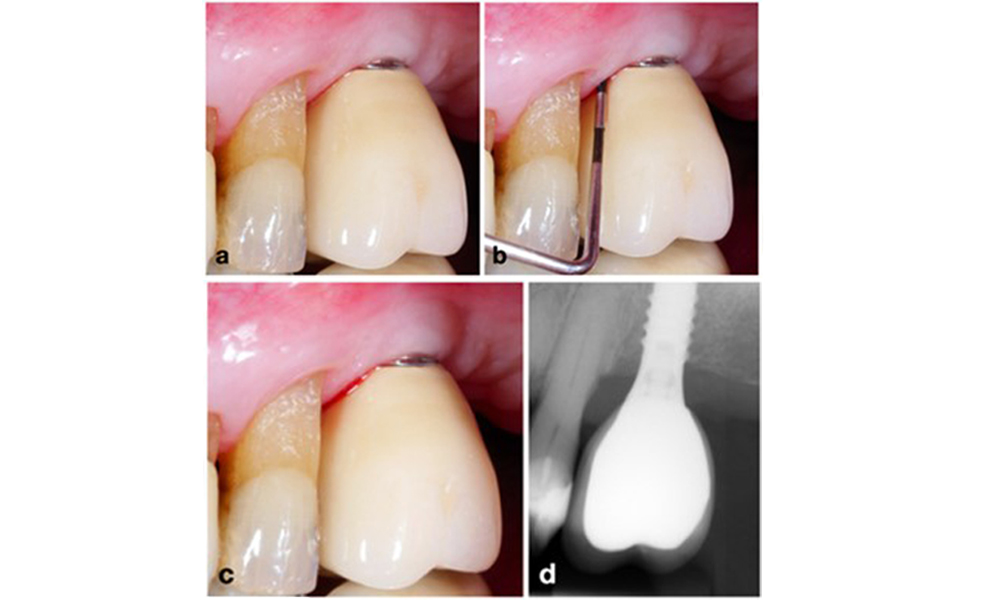

La péri-implantite est identifiée par (1) des signes d'inflammation similaires à la mucosite, (2) des preuves radiographiques de perte osseuse après la cicatrisation initiale et (3) une augmentation de la profondeur de sondage par rapport aux mesures prises peu après la mise en place de la reconstruction prothétique (figure 2). En l'absence de radiographies antérieures, un niveau osseux radiographique de ≥ 3 mm, accompagné d'un saignement au sondage et d'une profondeur de sondage ≥ 6 mm, indique une péri-implantite.

La perte osseuse attendue après la cicatrisation initiale, attribuée au remodelage de l'os marginal, varie en fonction de facteurs tels que le système ou le type d'implant. Par exemple, une perte osseuse de 1 à 2 mm est généralement considérée comme "normale" pour les implants au niveau de l'os avec une connexion externe (figure 2d, implant en position 23).